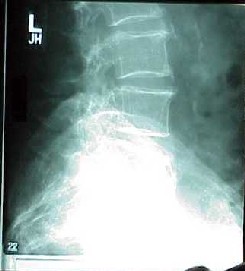

Osteoporosis

the bone progressively brittle. As bone is lost, the skeleton continues to have

a normal composition, but it becomes porous, hyper-mineralized and more fragile,

leading to spinal deformities (dowager's hump) and painful fractures of the

wrist, hip and spine.